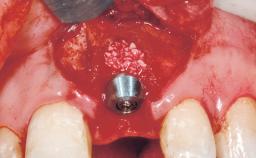

Late Flapless Placement of an Implant in a Maxillary Left Central Incisor Site

A 39-year-old male patient presented with a chief complaint of discomfort and gingival discoloration around his maxillary left central incisor. He was in good general health and was a non-smoker. His past dental history was significant because of the traumatic fracture of tooth 21 in a sporting accident at age 13. Initial dental treatment included endodontic therapy and a full-coverage restoration. The patient became symptomatic 5 years later, when structural failure of the tooth resulted in the dislodgment of the crown. Endodontic retreatment, apical surgery, and post-and-core restoration were performed.

Bone Volume | Deficient horizontally, requiring prior grafting |